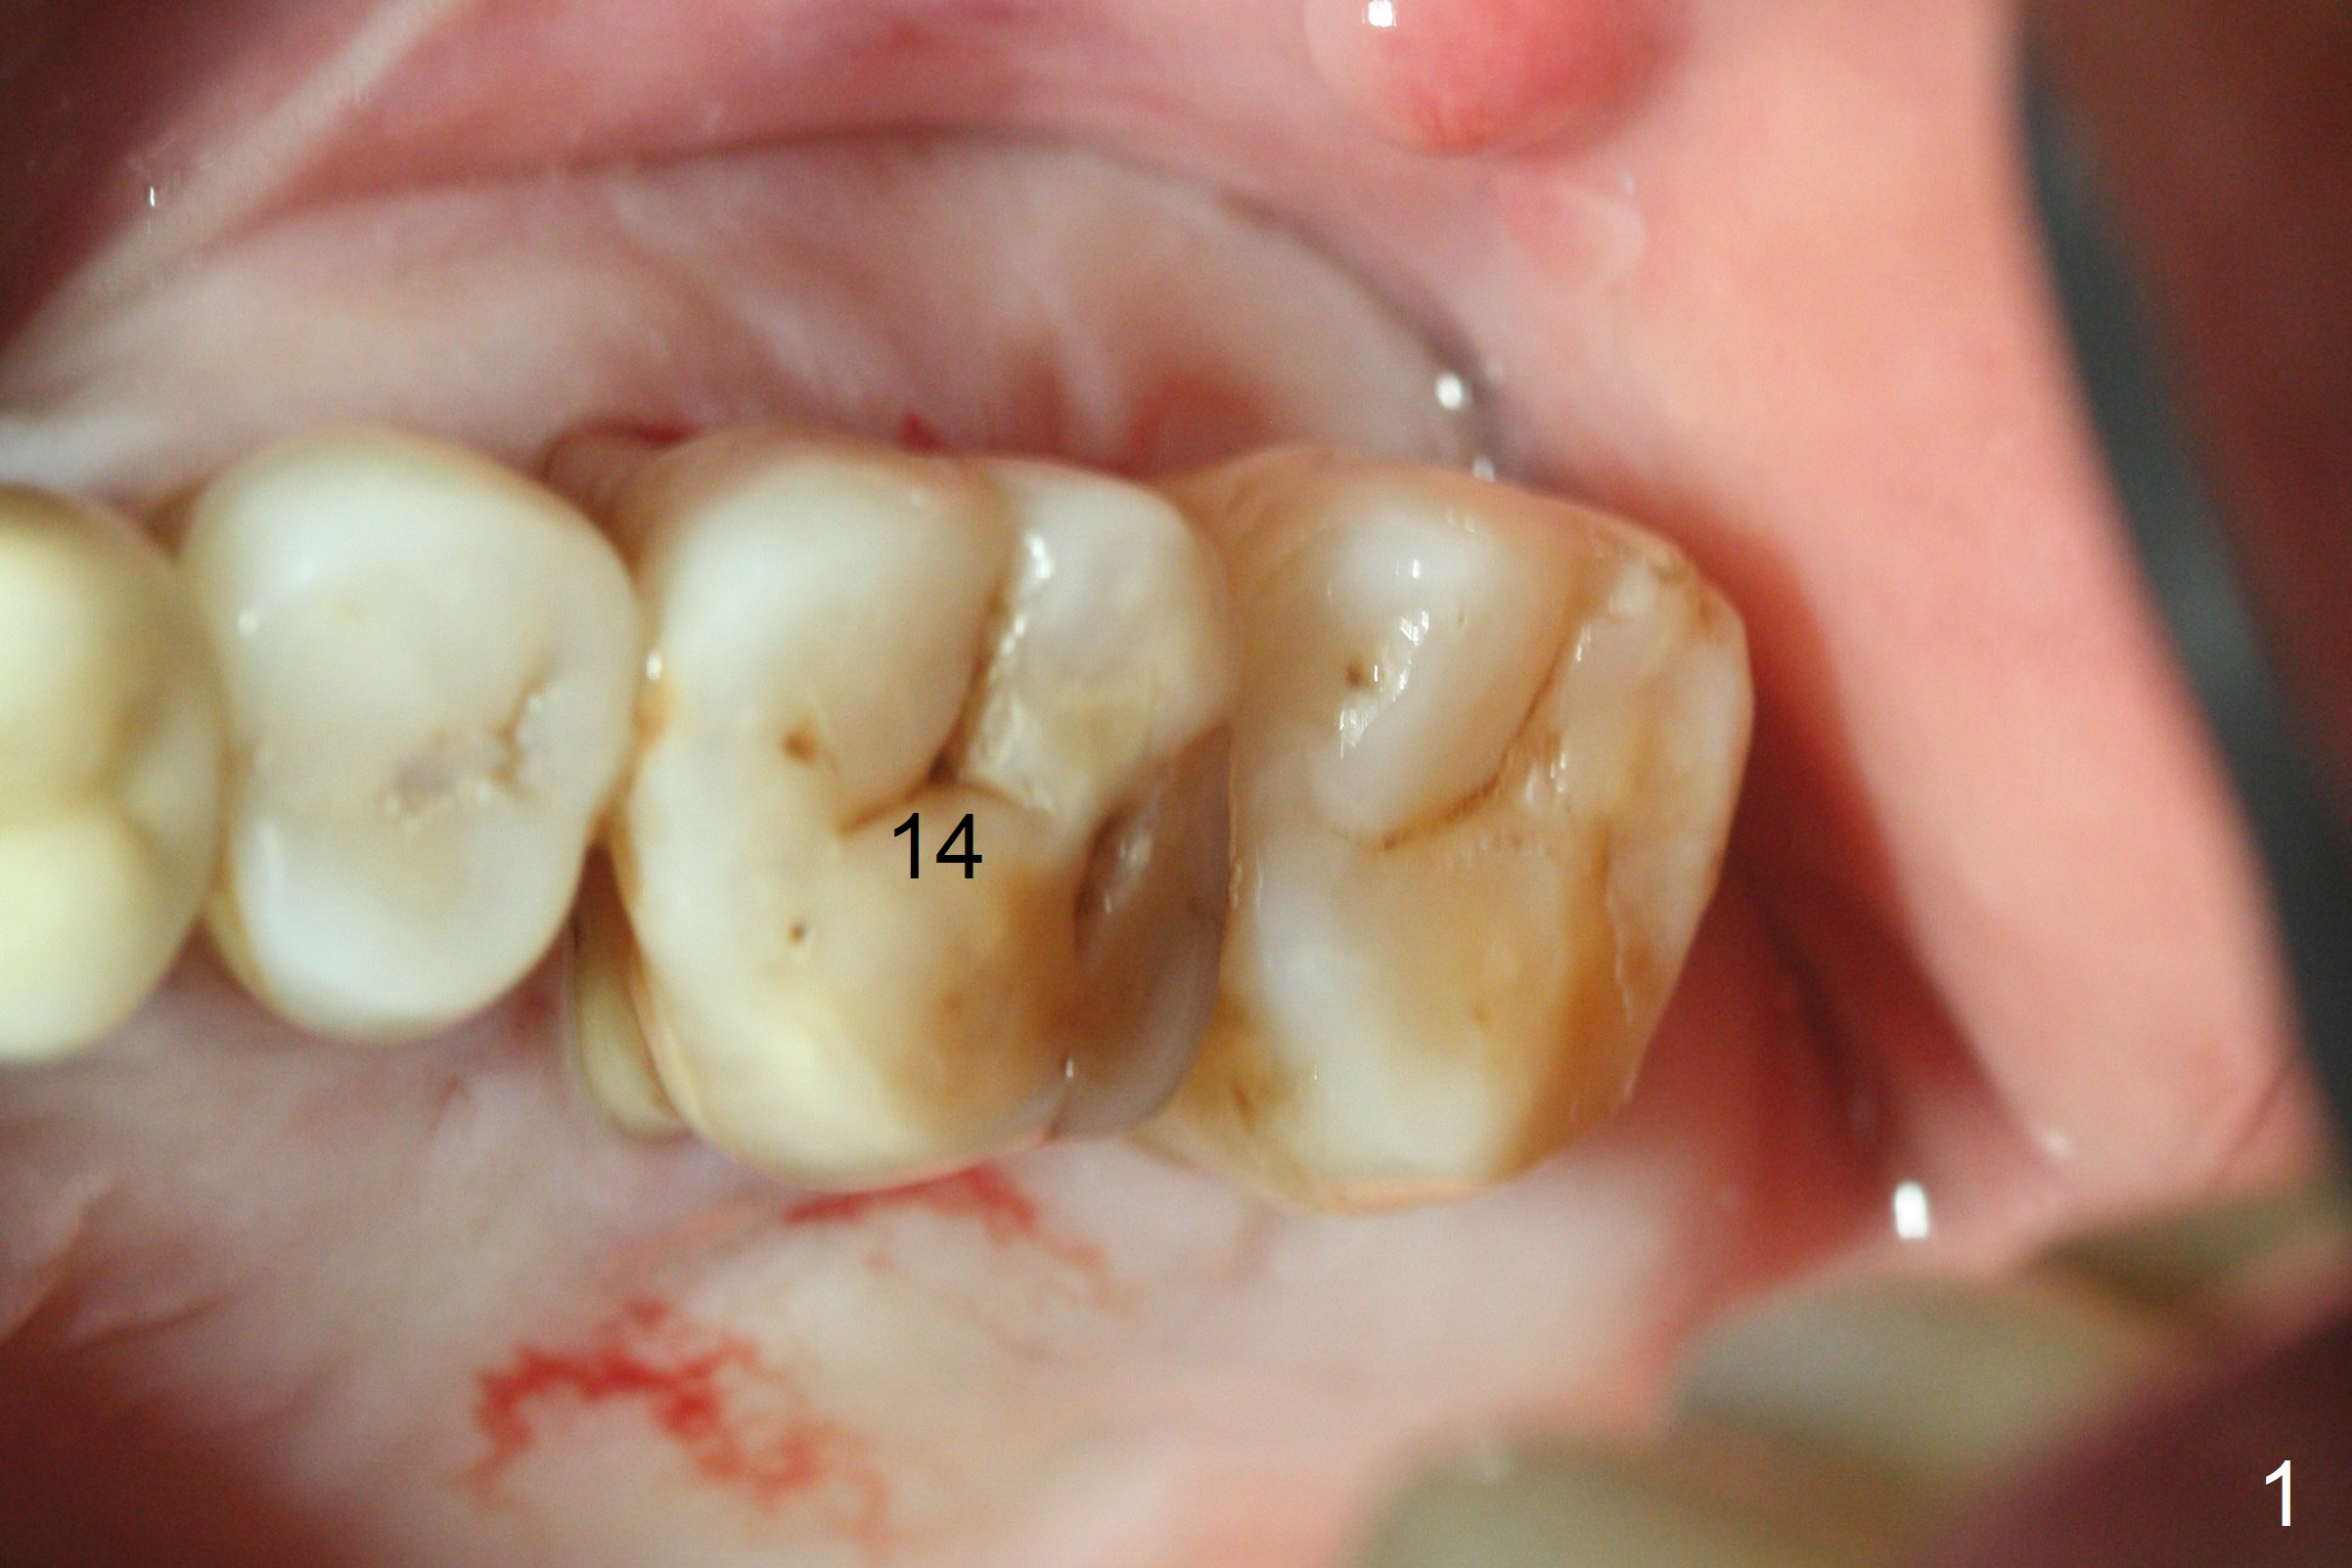

The ridge over the mobile tooth #14 is wide, suggesting bruxism pathogenesis (Fig.1). In spite of calculus over the roots of the extracted tooth (Fig.2), the septum remains. Osteotomy is initiated in the palatal slope of the septum (Fig.3,3' red dashed line). A 4.3 mm Magic Drill (MD) cannot bite into the bone probably because of the slope. Sequential osteotomy has to be done, starting with the smallest MD until 4.8 mm one. A 5x9 mm dummy implant is placed with 50 Ncm (Fig.4). To place 5x11 mm IBS implant (Fig.5), 5.3 mm MD has to be used; prior to implant placement, sinus lift is accomplished with mixture of autogenous bone and Vanilla graft (white *); more allograft (black *) is placed around the implant before insertion of a 6x5.7(3) mm abutment. More allograft is placed around the abutment (Fig.6 *) prior to an immediate provisional fabrication. The grafted bone appears to become the native bone, although at the low density, 6.5 months postop (Fig.7). The implant at #14 appears to have been placed in the middle of the alveolus buccopalatally (Fig.8).